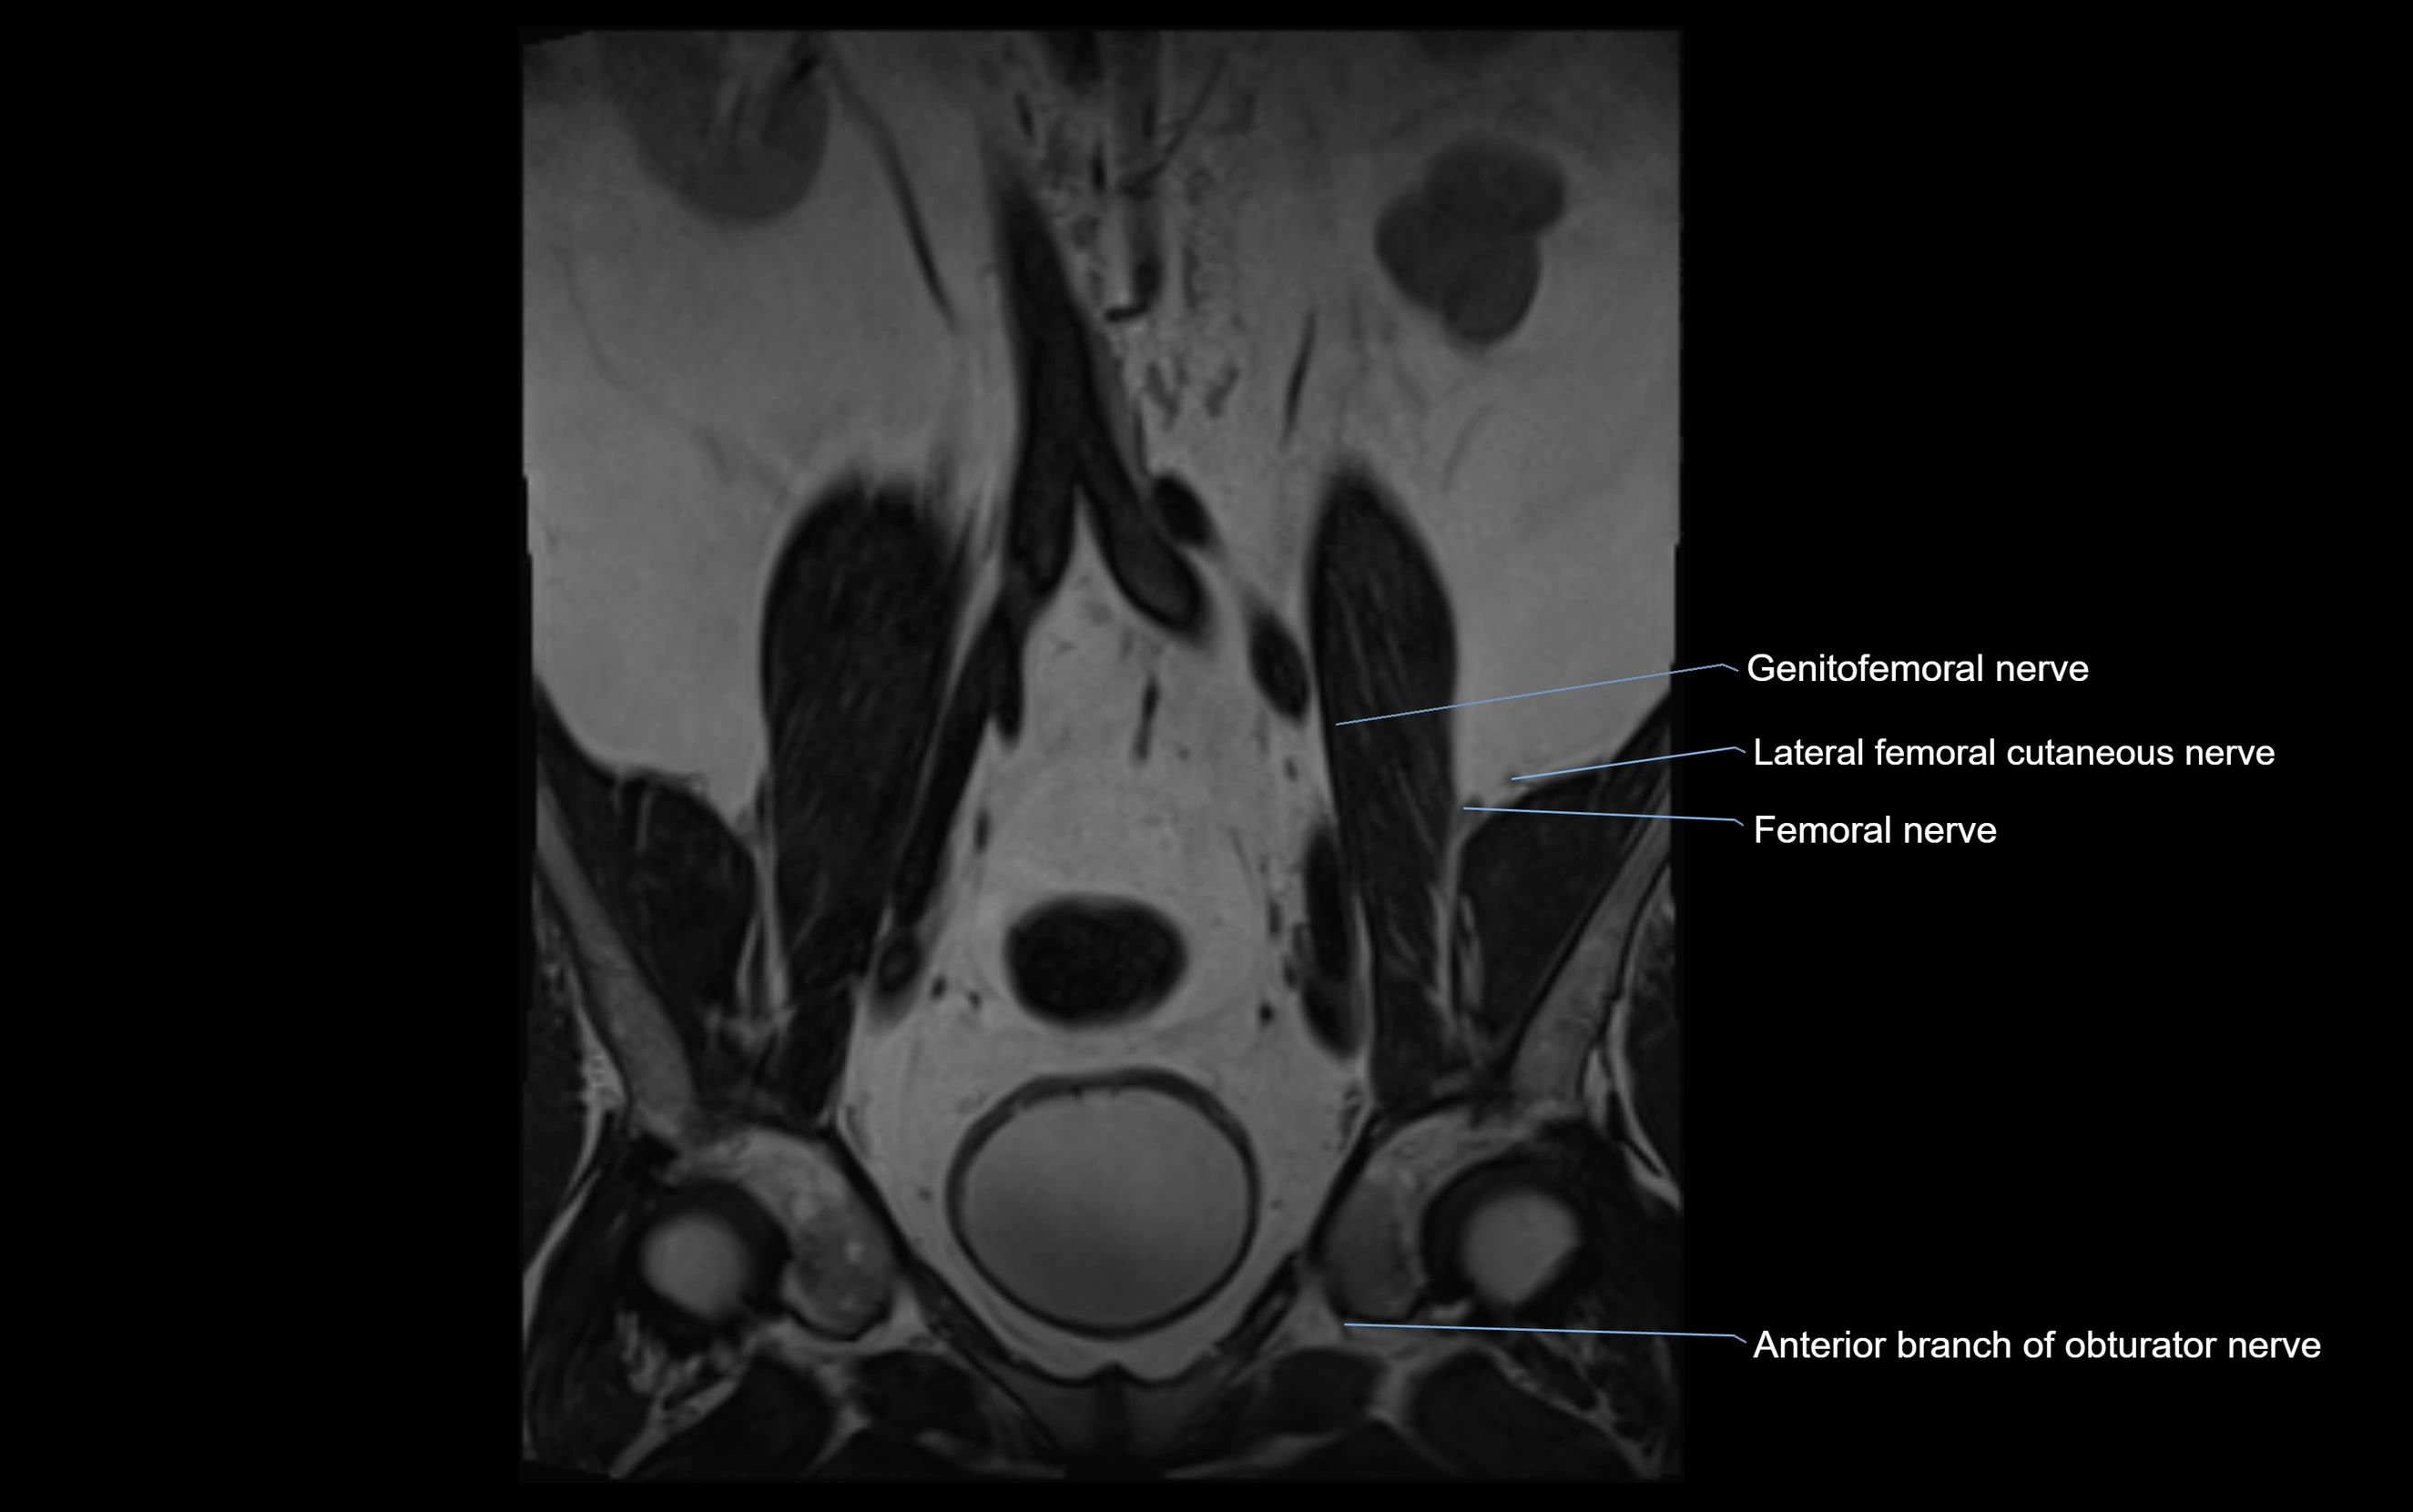

MRI image

image